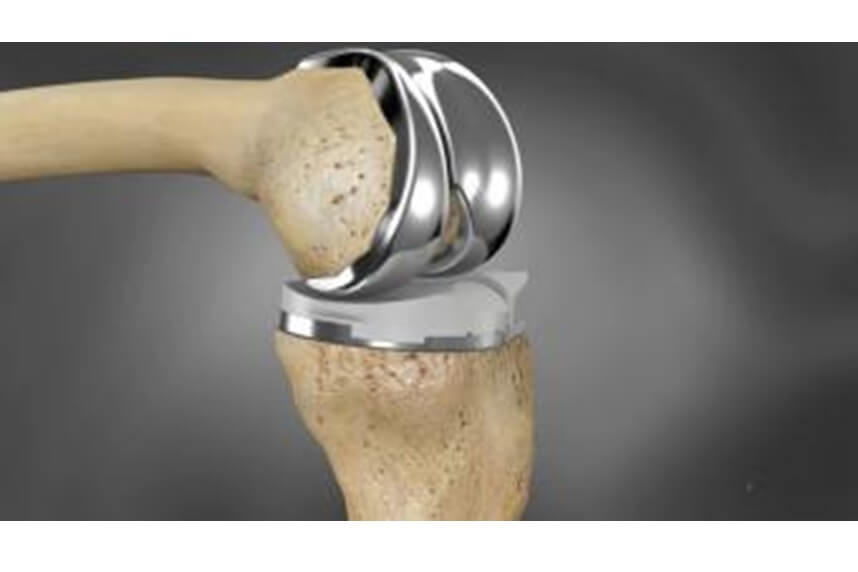

- Knee Replacement

This surgery is recommended in cases of severe knee osteoarthritis where pain is persistent and movement is severely affected, and where diagnostic X-rays have confirmed the severity.

Generally, this type of intervention is recommended for individuals over 60 years old due to the prosthesis's lifespan and the fact that as age increases, the demand for physical performance decreases. Knee replacement surgery should be postponed as long as possible for patients who continue to maintain sufficient functionality and have tolerable pain. In cases where osteoarthritis affects a young person's joint, procedures such as osteotomy are preferred as they correct load axes, reducing pressure on load-bearing joints.

When helping patients with their postoperative recovery, our primary goal is to restore the full range of motion, then muscle strength, and finally coordination through a personalized program of hydrokinesiotherapy and kinesitherapy. With this approach, we typically manage to get patients on their feet about 10-15 days after surgery and on the path to complete recovery.